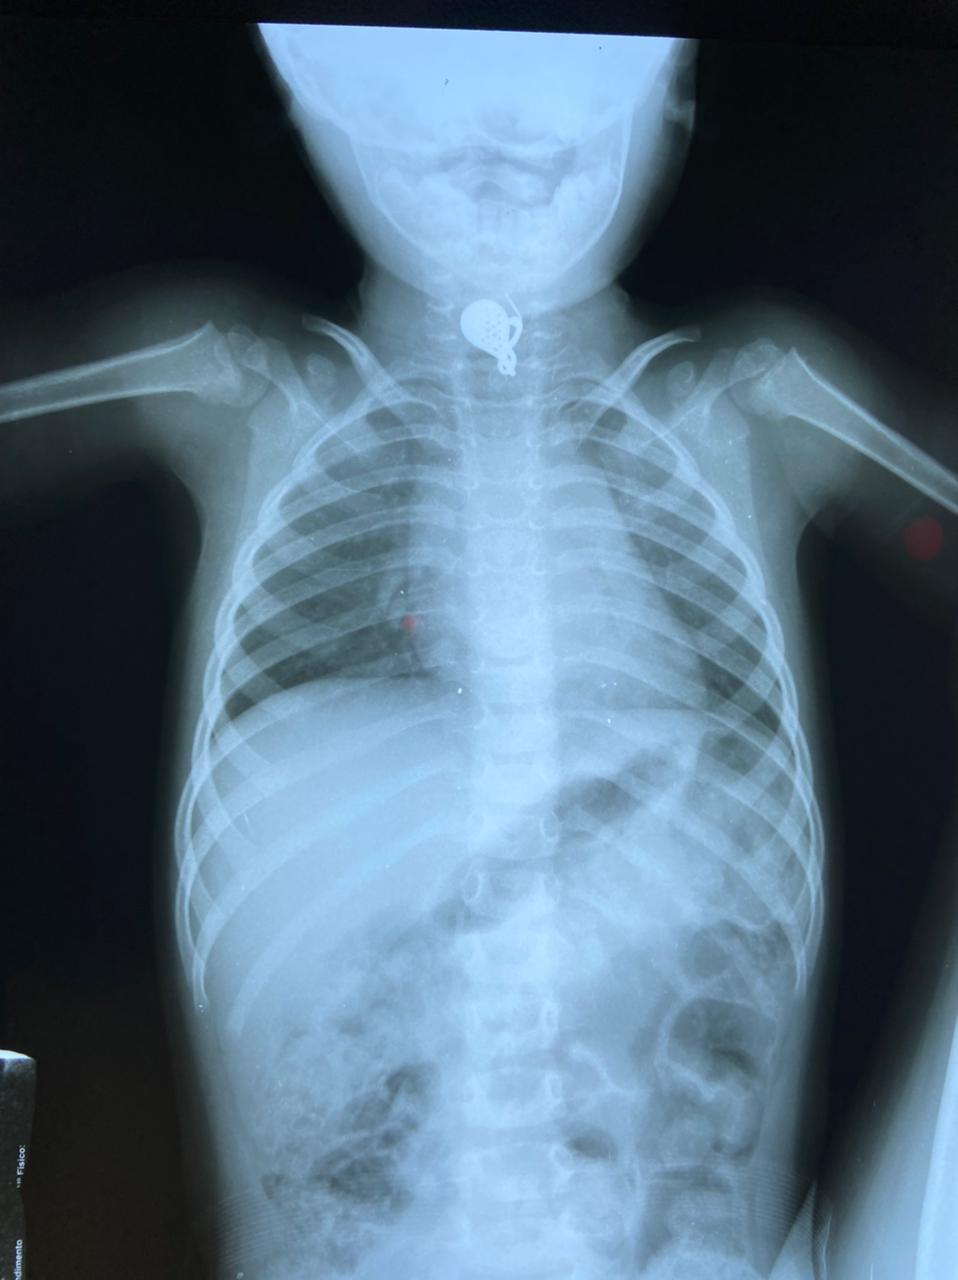

No exame de raio X a equipe conseguiu observar o ponto exato onde estava o brinco para fazer o procedimento. A menina já recebeu alta do HU de Maringá e voltou para a cidade de Paraíso do Norte com os pais.